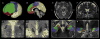

Deep brain stimulation of the subthalamic nucleus (STN) is a widely performed surgical treatment for patients with Parkinson's disease. The goal of the surgery is to place an electrode centered in the motor region of the STN while lowering the effects of electrical stimulation on the non-motor regions. However, distinguishing the motor region from the neighboring associative and limbic areas in individual patients using imaging modalities was until recently difficult to obtain in vivo. Here, using ultra-high field MR imaging, we have performed a dissection of the subdivisions of the STN of individual Parkinson's disease patients. We have acquired 7T diffusion-weighted images of seventeen patients with Parkinson's disease scheduled for deep brain stimulation surgery. Using a structural connectivity-based parcellation protocol, the STN's connections to the motor, limbic, and associative cortical areas were used to map the individual subdivisions of the nucleus. A reproducible patient-specific parcellation of the STN into a posterolateral motor and gradually overlapping central associative area was found in all STNs, taking up on average 55.3% and 55.6% of the total nucleus volume. The limbic area was found in the anteromedial part of the nucleus. Our results suggest that 7T MR imaging may facilitate individualized and highly specific planning of deep brain stimulation surgery of the STN.